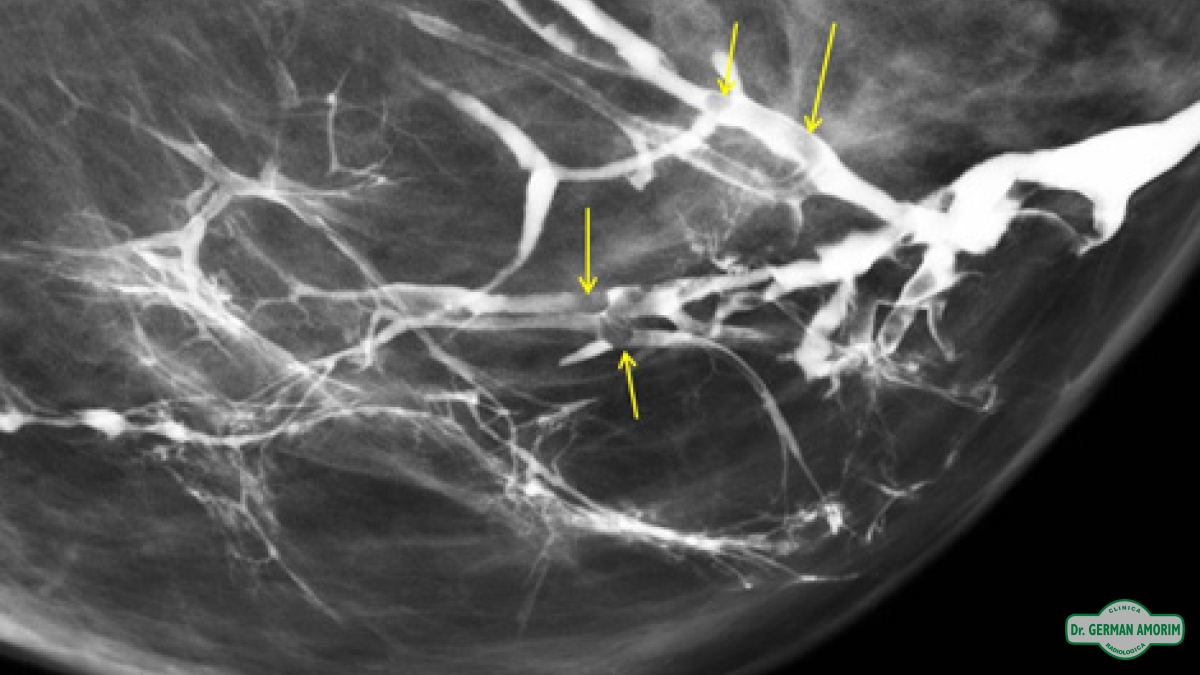

La lesión intraductal más frecuente es el papiloma y aunque el carcinoma intraductal tiene una frecuencia menor, al no poder distinguir entre ellas con este método de imagen, se recomienda la escisión quirúrgica. Es en este contexto que la galactografía sirve de mapa prequirúrgico para identificar correctamente el conducto patológico, la extensión de la lesión intraductal y la posible existencia de lesiones múltiples.

Entre las ventajas de esta técnica de imagen podemos mencionar la alta capacidad de definición de los ductos y de las posibles lesiones intraductales tras la administración de contraste, permitiendo así un mapa prequirúrgico para una escisión lo más selectiva posible.